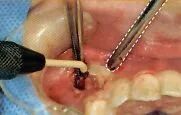

剥离同样如此,无论向几个方向插入牙挺。口腔卫生士最好事先预想一下会插入哪几个部分再使用吸唾器吸引。

牙挺拔牙时,牙槽骨和牙齿之间插入牙挺引起的牙齿脱臼

插入牙挺部位的视野一定要清晰

(插入前将牙挺置于牙槽骨和牙齿之间,插入时优先插入牙挺尖端)

确认完成缝合的部位是否有出血。由于牙周膜腔部分会出血,用吸唾器吸收牙槽骨和牙根之间的交界处(图10)。此外,向牙挺施加力的时候会出血,一定要使用吸唾器不厌其烦地吸引牙挺尖端部分血。

吸引牙周膜腔的出血时,一定要保证主治医生的的视野清晰。